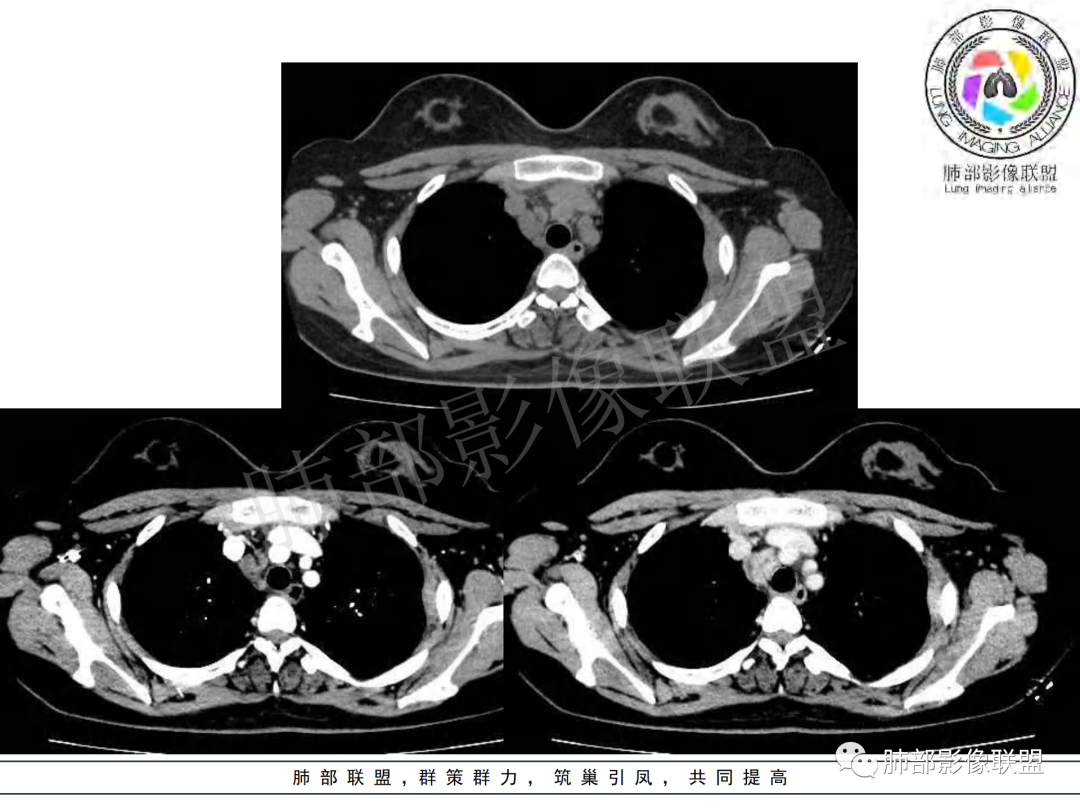

女,20,病程长达8月,发热、胸痛、右侧胸腔积液病史。胸部CT:右肺门旁不规则肿块影,右中间支气管腔内结节,纵隔多发淋巴结肿大;强化不均匀,灶性坏死灶,环形强化;右侧少量胸腔积液并局部肉芽肿样突起。年轻女性,长病程,多部位,考虑慢性炎症,结核?鉴别肿瘤。

年轻女性,慢性病程,发热、胸痛。右肺门旁不规则肿块影,纵隔多发淋巴结肿大;强化不均匀,环形强化;右侧少量胸腔积液;首先考虑结核,鉴别肿瘤,结节病。

慢性病程,前纵隔右肺门旁多发淋巴结肿大;强化不均匀,环形强化;右侧少量胸腔积液;考虑结核,鉴别结节病。

青年女性,发热、胸痛、右侧胸腔积液病史,病程8个月。曾多次抗炎后均有好转。CT:右肺门旁肿块影,双侧胸膜结节,纵隔多发淋巴结肿大,边缘模糊;增强渐进性明显强化,纵膈淋巴结较彻底坏死灶,边缘环形强化。考虑结核,鉴别恶性肿瘤。

女性,20岁。高热、畏寒。右肺上叶近肺门区不规则肿块,周围斑点、片小结节影伴肿大淋巴结,肿块包绕并突入右主支气管腔内,增强后肿块不均匀强化,淋巴结环形强化中心低密度,考虑结核。

纵隔肺门及两侧胸膜强化结节,支气管管腔不通畅。结核能解释临床及影像,就是强化有点猛,这个妖怪真不好说。恶性如类癌/高级别黏表/恶性间皮也要考虑。

无典型结核病中毒症状的成人纵隔淋巴结结核的文献报道不在少数,因此,当临床中遇到症状不典型的患者时,不能轻易排除结核病的诊断,胸部增强CT对本病的诊断与鉴别诊断有一定价值。增强CT扫描时,肿大的淋巴结呈典型的边缘强化或分割样强化,这是纵隔淋巴结结核极具特征性表现,其强化形式与淋巴结内血管及肉芽组织数量及分布有关。淋巴结环形强化或分割样强化的病理基础是淋巴结外周或液化区分隔带有毛细血管丰富的肉芽组织,而无强化的液化区则为无结构的干酪样坏死物质。

本例患者,年轻女性,慢性病程,多次抗感染治疗效果不佳,实验室检查示白细胞及中性粒细胞不高,不支持普通细菌感染,虽然肺泡灌洗液X-Pert检测阴性,结合患者胸部CT结核感染亦不能排除,胸部CT主要表现为右侧肺门及纵隔淋巴结肿大,仔细观察不难发现右中间支气管内新生物凸向管腔内,增强扫描,右肺门(10R)及纵隔淋巴结(2R,4R)明显不均匀强化,内部呈不规则低密度无强化区,被周边高强化区包绕(环形强化)的特点,首先应当想到纵隔淋巴结结核诊断。淋巴结分布亦不符合肺部恶性肿瘤迁徙途径。